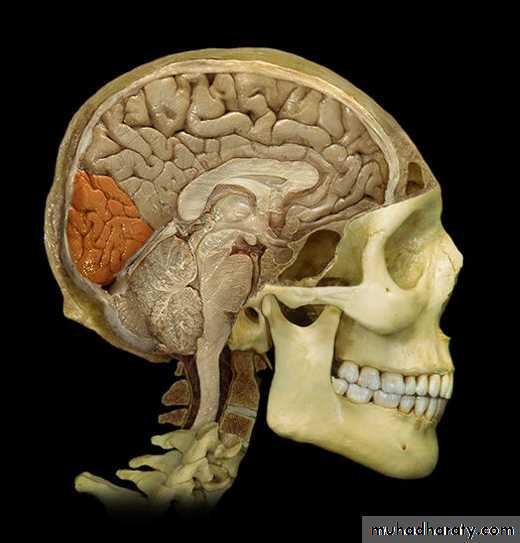

Lobes of Cerebral Hemisphere

Five lobes

Frontal lobe

Parietal lobe

Temporal lobe

Occipital lobe

Insular lobe

Parietal lobeOccipital lobe